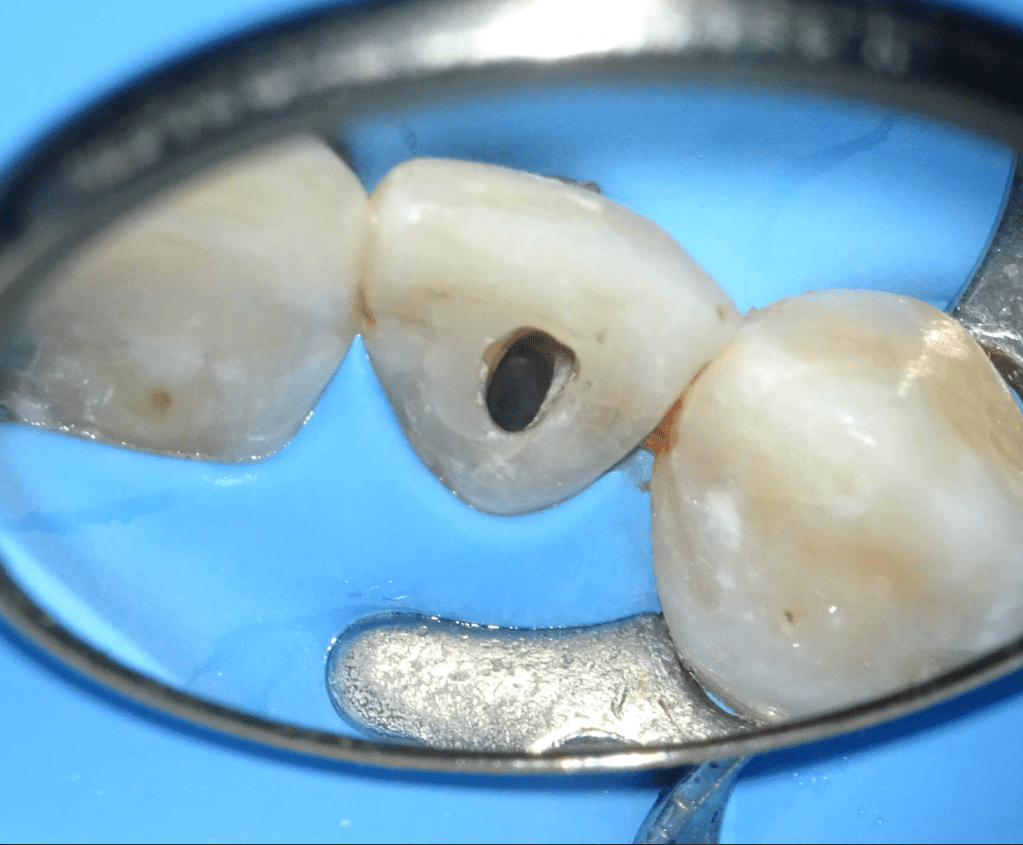

Pulpotomía biodentine + reco preendio